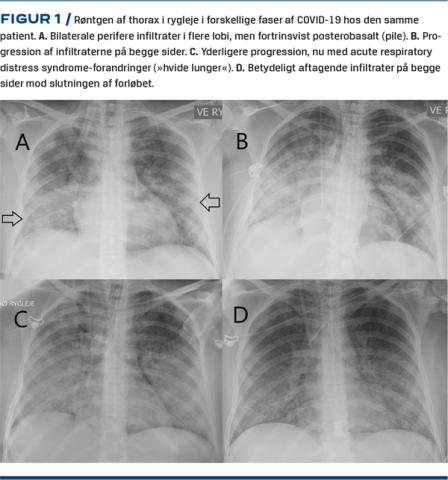

Perifert beliggende matglasinfiltrater (Figur 2A-D) er det hyppigste fund efterfulgt af konsolideringer senere i forløbet (Figur 3C) [5, 8-12]⁠. Der ses typisk vaskulær forstørrelse i matglasinfiltraterne (Figur 2B) [13], hvilket formentlig repræsenterer interstitielt ødem/inflammation peribronkovaskulært og/eller muligvis en øget kardiameter på grund af hyperæmi. Ofte er matglasinfiltraterne afrundede (Figur 2C og D). I nogle tilfælde er de mere centralt beliggende. Multilobær og bilateral placering er hyppigst – særligt når sygdommen progredierer (10,12). Der kan som ved andre pneumoniske sygdomme findes luftbronkogram i infiltraterne [14-16]. Der kan ved progression ses crazy paving(Figur 3B)og retikulering med traktionsbronkieektasier (Figur 3 D) [10, 14, 16, 17] samt reverse halo sign(Figur 3F) [12, 13]. Et perilobulært mønster med arcade-like sign(Figur 3 E) kan også ofte ses, når sygdommen peaker omkring 10-14 dage efter symptomudbrud [18], hvilket indikerer sekundær organiserende pneumoni som det også er set ved lignende virale infektioner som SARS-CoV, MERS-CoV og H1N1-influenzavirus [19, 20]. Derimod ses pleural ansamling, mediastinal lymfeknudeforstørrelse samt pneumothorax sjældent ved COVID-19 [8, 13, 16, 21, 22], og disse fund bør give mistanke om bakteriel superinfektion eller andre sygdomme [7]. I et studie med 424 patienter var pleural fortykkelse, pleuraeffusioner, mediastinal lymfeknudesvulst samt luftbronkogram signifikant hyppigere ved andre typer af viral pneumoni end COVID-19 [13]. Tree-in-bud-forandringer samt kaviterende infiltrater er ikke hyppige [9, 11].